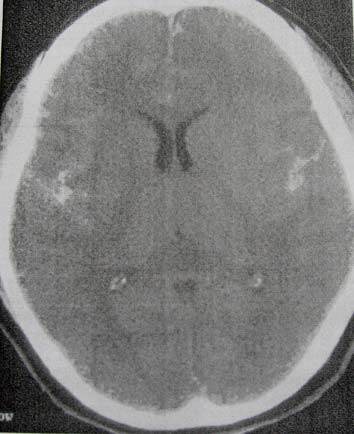

A. Astrositoma pilositik

B. Meduloblastoma

C. Infark Subakut

D. Penyakit LHERMITTE-DUCLOS

E. Ependimoma